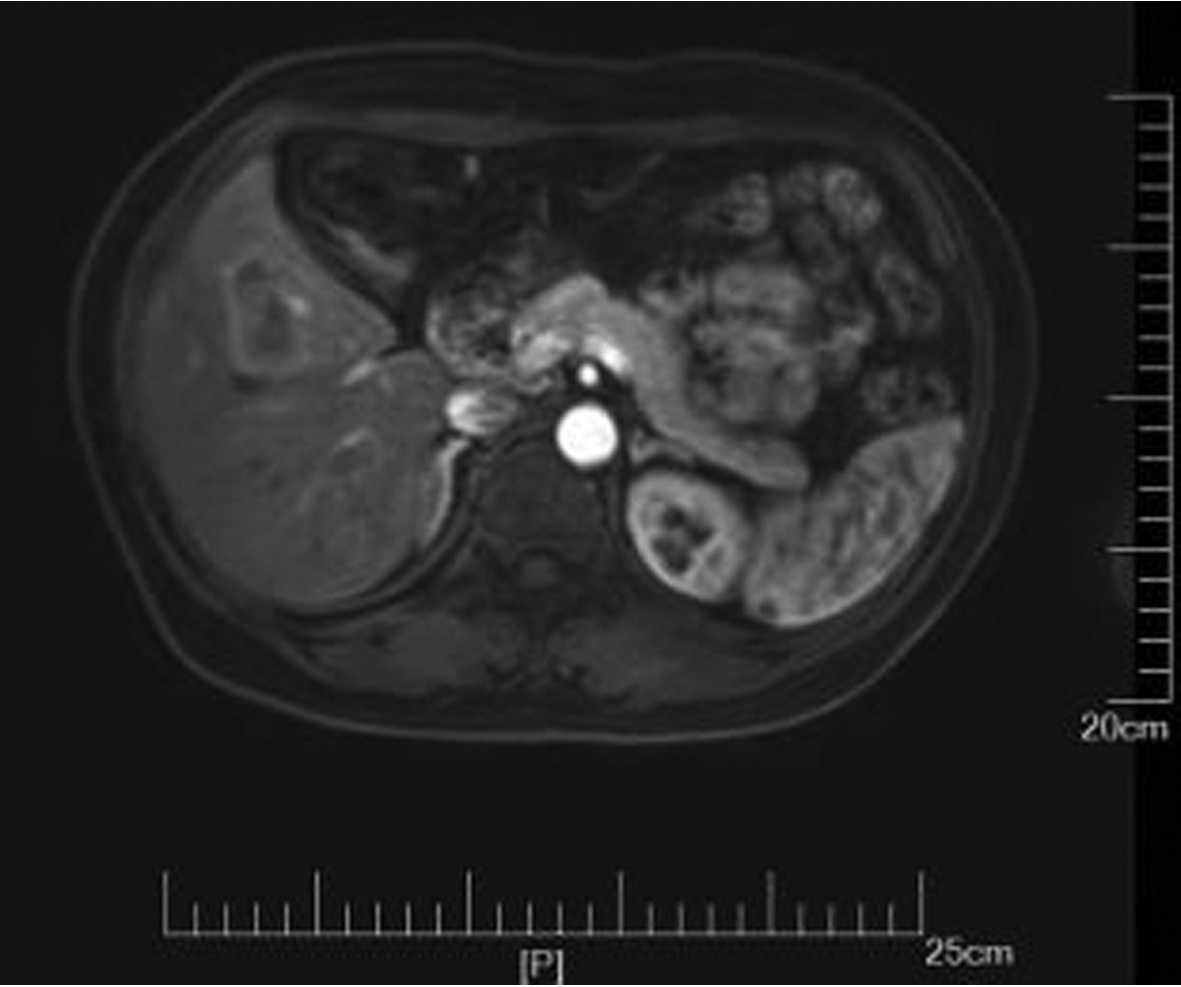

乙型肝炎肝硬化上消化道出血的ΔCT特征性表现及预测模型的建立

李俊杰, 孙岩岩, 李将宏, 郑虹

2022, 38(5): 1081-1085. DOI: 10.3969/j.issn.1001-5256.2022.05.020

摘要(1053) HTML (308) PDF (2671KB)(64)

摘要:

目的  本研究旨在寻找乙型肝炎肝硬化CT特征,建立肝硬化上消化道出血预测模型,预测出血风险。  方法  回顾性分析2015年1月—2021年6月天津市第一中心医院101例型肝炎肝硬化患者的数据,将其分为上消化道出血组(P=58)及非出血组(n=43)。比较两组间实验室检查以及强化CT检查测的平扫期、动脉期、门脉期以及静脉期的CT值,并计算各期间CT值的变化(ΔCT)。计量资料两组间的比较使用t检验或Mann-Whitney U检验;使用logistic回归分析方法,预测相关危险因素;通过计算受试者工作特征曲线下的面积评估模型辨别力,而模型校准则通过Hosmer-Lemeshow确定。在多变量logistic回归分析结果的基础上,使用Rstudio4.1.2软件的R包构建预测的列线图模型,并绘制相应的ROC曲线、校准曲线以及临床决策曲线。  结果  非出血组血清TBil、WBC、PLT水平与出血组比较,差异均有统计学意义(P值均<0.05);两组在肝-Plain、脾-P-Plain、脾-P-A ΔCT值存在统计学差异(P值均<0.05)。单因素logistic分析结果显示,白细胞(OR=0.770,95%CI:0.624~0952, P=0.016)、血小板(OR=0.979,95%CI:0.965~0.994, P=0.006)、肝脏平扫期(OR=1.142,95%CI:1.058~1.233, P=0.001)、脾脏门脉期-平扫ΔCT值(OR=0.979,95%CI:0.959~1.000, P=0.050)、脾脏门脉期-动脉期ΔCT值(OR=0.979,95%CI:0.944~0.994, P=0.015)在乙型肝炎肝硬化患者发生上消化道出血与未出血两者之间差异具有统计学意义。多因素logistic分析结果显示血小板(OR=0.968,95%CI:0.944~0.993, P=0.011)、肝脏平扫期(OR=1.148,95%CI:1.047~1.259, P=0.003)、脾脏门脉期-动脉期ΔCT值(OR=0.951,95%CI:0.908~0.995, P=0.030)为上消化道出血的独立危险因素。基于多因素logistic分析结果,构建了乙型肝炎肝硬化上消化道出血的预测模型并绘制校准曲线。该模型的受试者特征曲线下面积为0.801,cut-off值为0.433,其对应的敏感度是81.4%,特异度是77.6%。模型的校准曲线与理想曲线贴合良好。  结论  乙型肝炎肝硬化肝脏具有特殊的ΔCT变化,通过ΔCT构建的预测模型对于乙型肝炎肝硬化上消化道出血具有良好的预测能力。